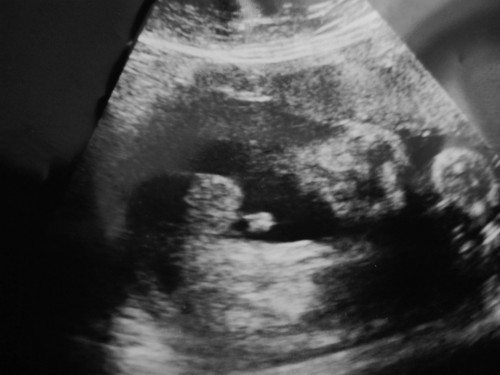

ยังงี้มองออกไหมคะ ว่าเพศอะไร

ช่วยดูหน่อยคะแม้ว่า บ้านนี้หญิงหรือชาย

คิดว่าน่าจะเป็นผู้ชายนะค่ะแม่